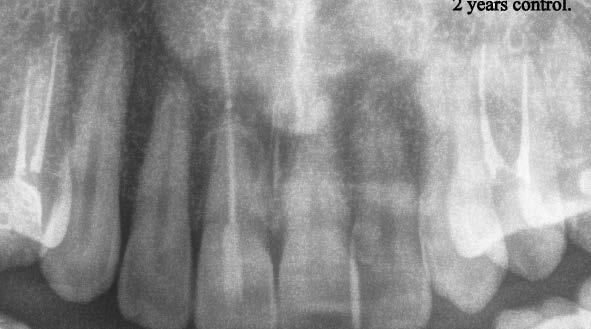

A páciens panaszai a kezelést követően megszűntek. A 11. és 12. ábrán a hat hónapos, illetve a kétéves kontroll látható.

9. ábra: A gyökértömés készítése. 10. ábra: Kontroll röntgenfelvétel az üvegszálas csappal. – 11. ábra: Hat hónapos kontroll. 12. ábra: Kétéves kontroll. 10 11